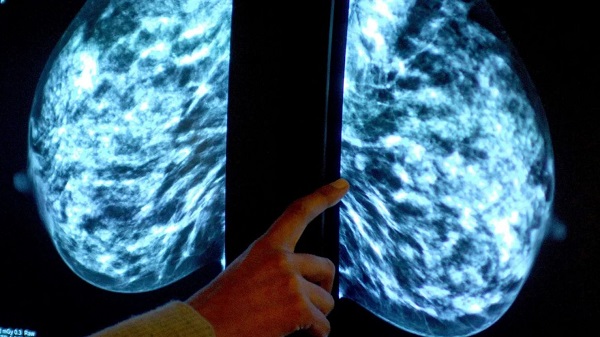

Un reciente estudio publicado en la revista The Lancet demuestra que la radioterapia tras la cirugía de cáncer de mama puede reducir significativamente la reaparición de tumores en el mismo seno durante una década. El estudio, realizado por investigadores de la Universidad de Edimburgo, destaca que la radioterapia es eficaz en la prevención de recaídas tempranas en mujeres con cáncer de mama en etapa inicial.

El ensayo clínico escocés, iniciado en los años 80, involucró a 585 mujeres menores de 70 años y con tumores de hasta 4 cm. Los resultados revelaron que el grupo que recibió radioterapia mostró un 16% de recurrencia, en comparación con el 36% en quienes no la recibieron. Este hallazgo refuerza la importancia de la radioterapia como tratamiento adyuvante tras la cirugía de conservación de senos.